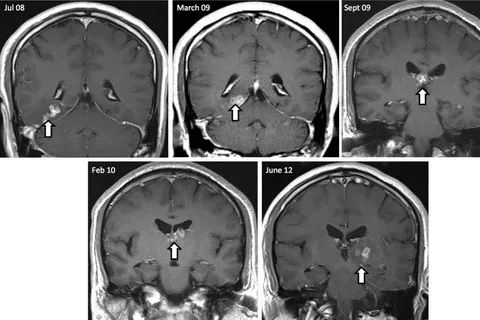

Imaging is key in finding brain lesions. MRI (Magnetic Resonance Imaging) and CT (Computed Tomography) scans are main tools. MRI spots soft tissue issues well, while CT scans are fast and used in emergencies.

MRI gives us clear brain pictures. It shows where, how big, and what kind of lesions are. It can tell if it’s a tumor, cyst, or inflammation. CT scans are great for finding bleeding, calcifications, and bone problems.